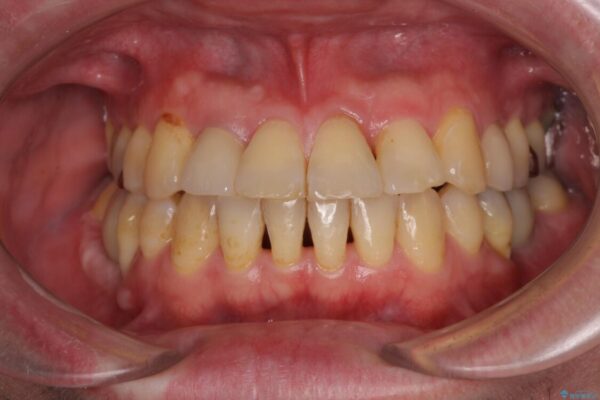

奥歯のセラミックがすぐに壊れる 欠損した奥歯へのインプラント治療

奥歯のセラミックがすぐに壊れる 欠損した奥歯へのインプラント治療 ビフォー 奥歯のセラミックがすぐに壊れる 欠損した奥歯へのインプラント治療 アフター

歯が欠損したままの奥歯のクラウンが欠けているとのことで来院された患者様です。